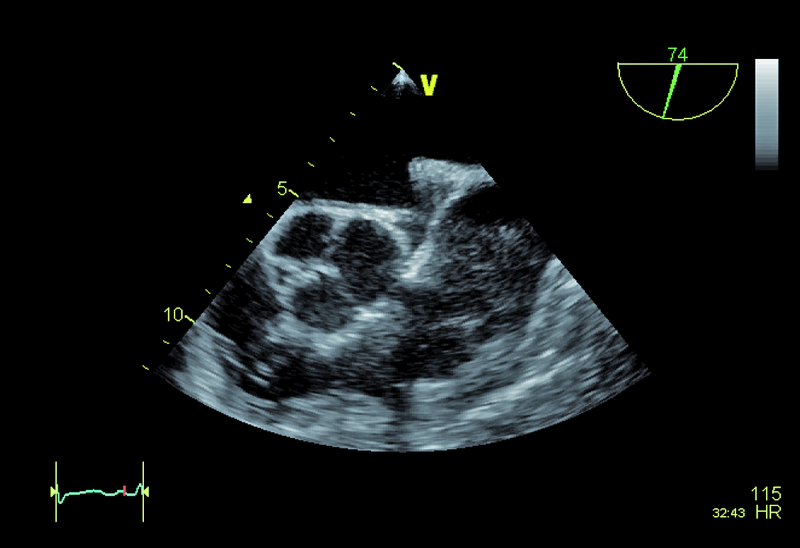

Pacjent, lat 60, z wywiadem nadciśnienia tętniczego, wieloletni palacz, został przyjęty do kliniki w celu oceny układu krążenia po przebytym rok wcześniej udarze mózgu. W przebiegu udaru obserwowano afazję ruchową, niedowład centralny nerwu VII, niedowład prawej kończyny górnej. Chory był intensywnie rehabilitowany, co przyczyniło się do stopniowego ustąpienia zaburzeń mowy oraz istotnej poprawy ruchomości prawej kończyny górnej. W tomografii komputerowej stwierdzono obszar hipodensyjny na pograniczu płata ciemieniowego i potylicznego lewej półkuli mózgu. Spektralne badanie doplerowskie tętnic szyjnych i kręgowych nie wykazało istotnych hemodynamicznie zaburzeń przepływu. Opiekujący się pacjentem neurolodzy podejrzewali, że przyczyną udaru mógł być przetrwały otwór owalny (patent foramen ovale, PFO). W wykonanych w klinice badaniach echokardiograficznych – przezklatkowym i przezprzełykowym – przegroda międzyprzedsionkowa była szczelna. Jama lewej komory była niepowiększona, a grubość mięśnia graniczna. Zwracało uwagę nieznaczne upośledzenie kurczliwości mięśnia komory (EF=50%) oraz poszerzenie aorty do 42 mm.

Wiek pacjenta, palenie tytoniu oraz chwiejne nadciśnienie tętnicze nakazują wykluczyć a priori tzw. kryptogenny udar mózgu. Przegroda międzyprzedsionkowa u chorego była szczelna, choć w badaniu przezprzełykowym (TOE) opisano śladowy kanał przetrwałego otworu owalnego (PFO), bez przechodzenia kontrastu ze strony prawej na lewą. Badanie przezprzełykowe pozwoliło także wykluczyć skrzeplinę w jamach serca (ryc. 1 – uszko lewego przedsionka) oraz istotne zmiany organiczne zastawki aortalnej (ryc. 2, 3). Prawdopodobną przyczyną udaru były nasilone zmiany miażdżycowe w łuku aorty z towarzyszącymi owrzodzeniami ściany naczynia (ryc. 4, 5). Warto zaznaczyć, że zmiany będące zgrubieniem błony wewnętrznej bywają dynamiczne i nie można wykluczyć powstawania ruchomych składowych (skrzeplin) na dużych elementach owrzodzenia. W diagnostyce miażdżycowego uszkodzenia aorty metodą z wyboru jest badanie przezprzełykowe, pozwalające zidentyfikować dzięki wysokiej rozdzielczości obrazu drobne, nawet kilkumilimetrowe owrzodzenia. Warto zaznaczyć, że badanie przezklatkowe nie dostarcza tak wyraźnego i jednoznacznego obrazu (ryc. 6). Korzyść z badania echokardiograficznego jest bez wątpienia większa niż z badania TK czy MR, ze względu na możliwość oceny ruchomości blaszek w czasie rzeczywistym. W rutynowej ocenie zwraca się uwagę na grubość blaszki miażdżycowej, obecność owrzodzeń, zwapnień oraz nałożonych ruchomych ech odpowiadających skrzeplinom – stanowiących tzw. potencjał zatorowy blaszki. Uważa się, że średnica blaszki przekraczająca 4 mm ma większy potencjał zatorowy niż owrzodzenie płytkie (w przedstawionym przypadku średnica blaszki wynosiła 7 mm). Dowiedziono ponadto, że w przypadku blaszek nieuwapnionych – jak w opisanej sytuacji – ryzyko zatoru jest większe niż w przypadku blaszek uwapnionych. Leczenie antykoagulacyjne w takim wypadku jest uzasadnione. Konieczne jest także włączenie dużej dawki statyn mimo braku zmian miażdżycowych w tętnicach wieńcowych (wykonano koronarografię). Ocena układu krążenia u pacjenta po przebytym incydencie zatorowym do OUN powinna być kompleksowa i powinna uwzględniać wszystkie możliwe nieprawidłowości.